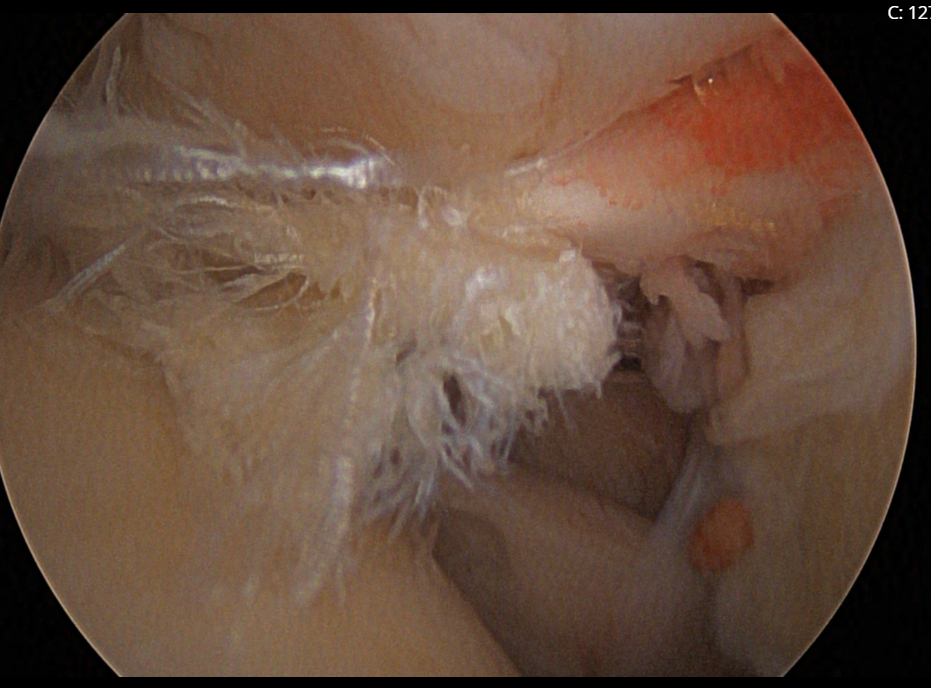

Rotator Cuff Tear

In a typical shoulder arthroscopy procedure, Dr. Cirino may perform several different types of repairs, depending on the diagnosis. Rotator cuff repair is one of the most common procedures performed arthroscopically. Dr. Cirino reattaches the torn tendon to the bone using suture anchors, which are small devices that hold the tendon in place during the healing process. Any bone spurs that may have caused or contributed to the tendon tear are debrided. The long head of the biceps tendon, located beneath the rotator cuff, is often repaired as part of the procedure.